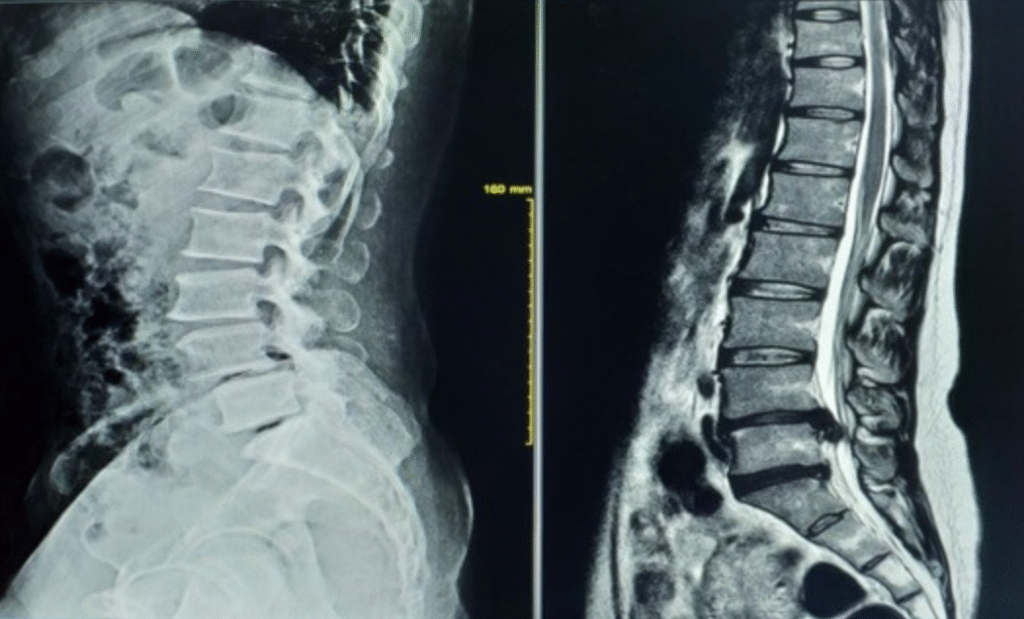

画像検査は骨や椎間板、神経などの構造的な異常を確認するのには有効ですが、筋肉の緊張や姿勢の問題、心理的な要因など、画像では捉えきれない原因が多く存在します。

レントゲンやMRIは、骨や椎間板、神経の圧迫などの構造的な異常を確認するのには適しています。しかし、筋肉の緊張や姿勢の歪み、神経の過敏性など、機能的な問題や心理的要因は画像では確認できません。

画像検査で異常が見つかっても、それが必ずしも痛みの原因であるとは限りません。例えば、椎間板ヘルニアがあっても無症状の人もいれば、軽度の異常でも強い痛みを感じる人もいます。つまり、構造的な異常と痛みの関連性は明確ではないのです。